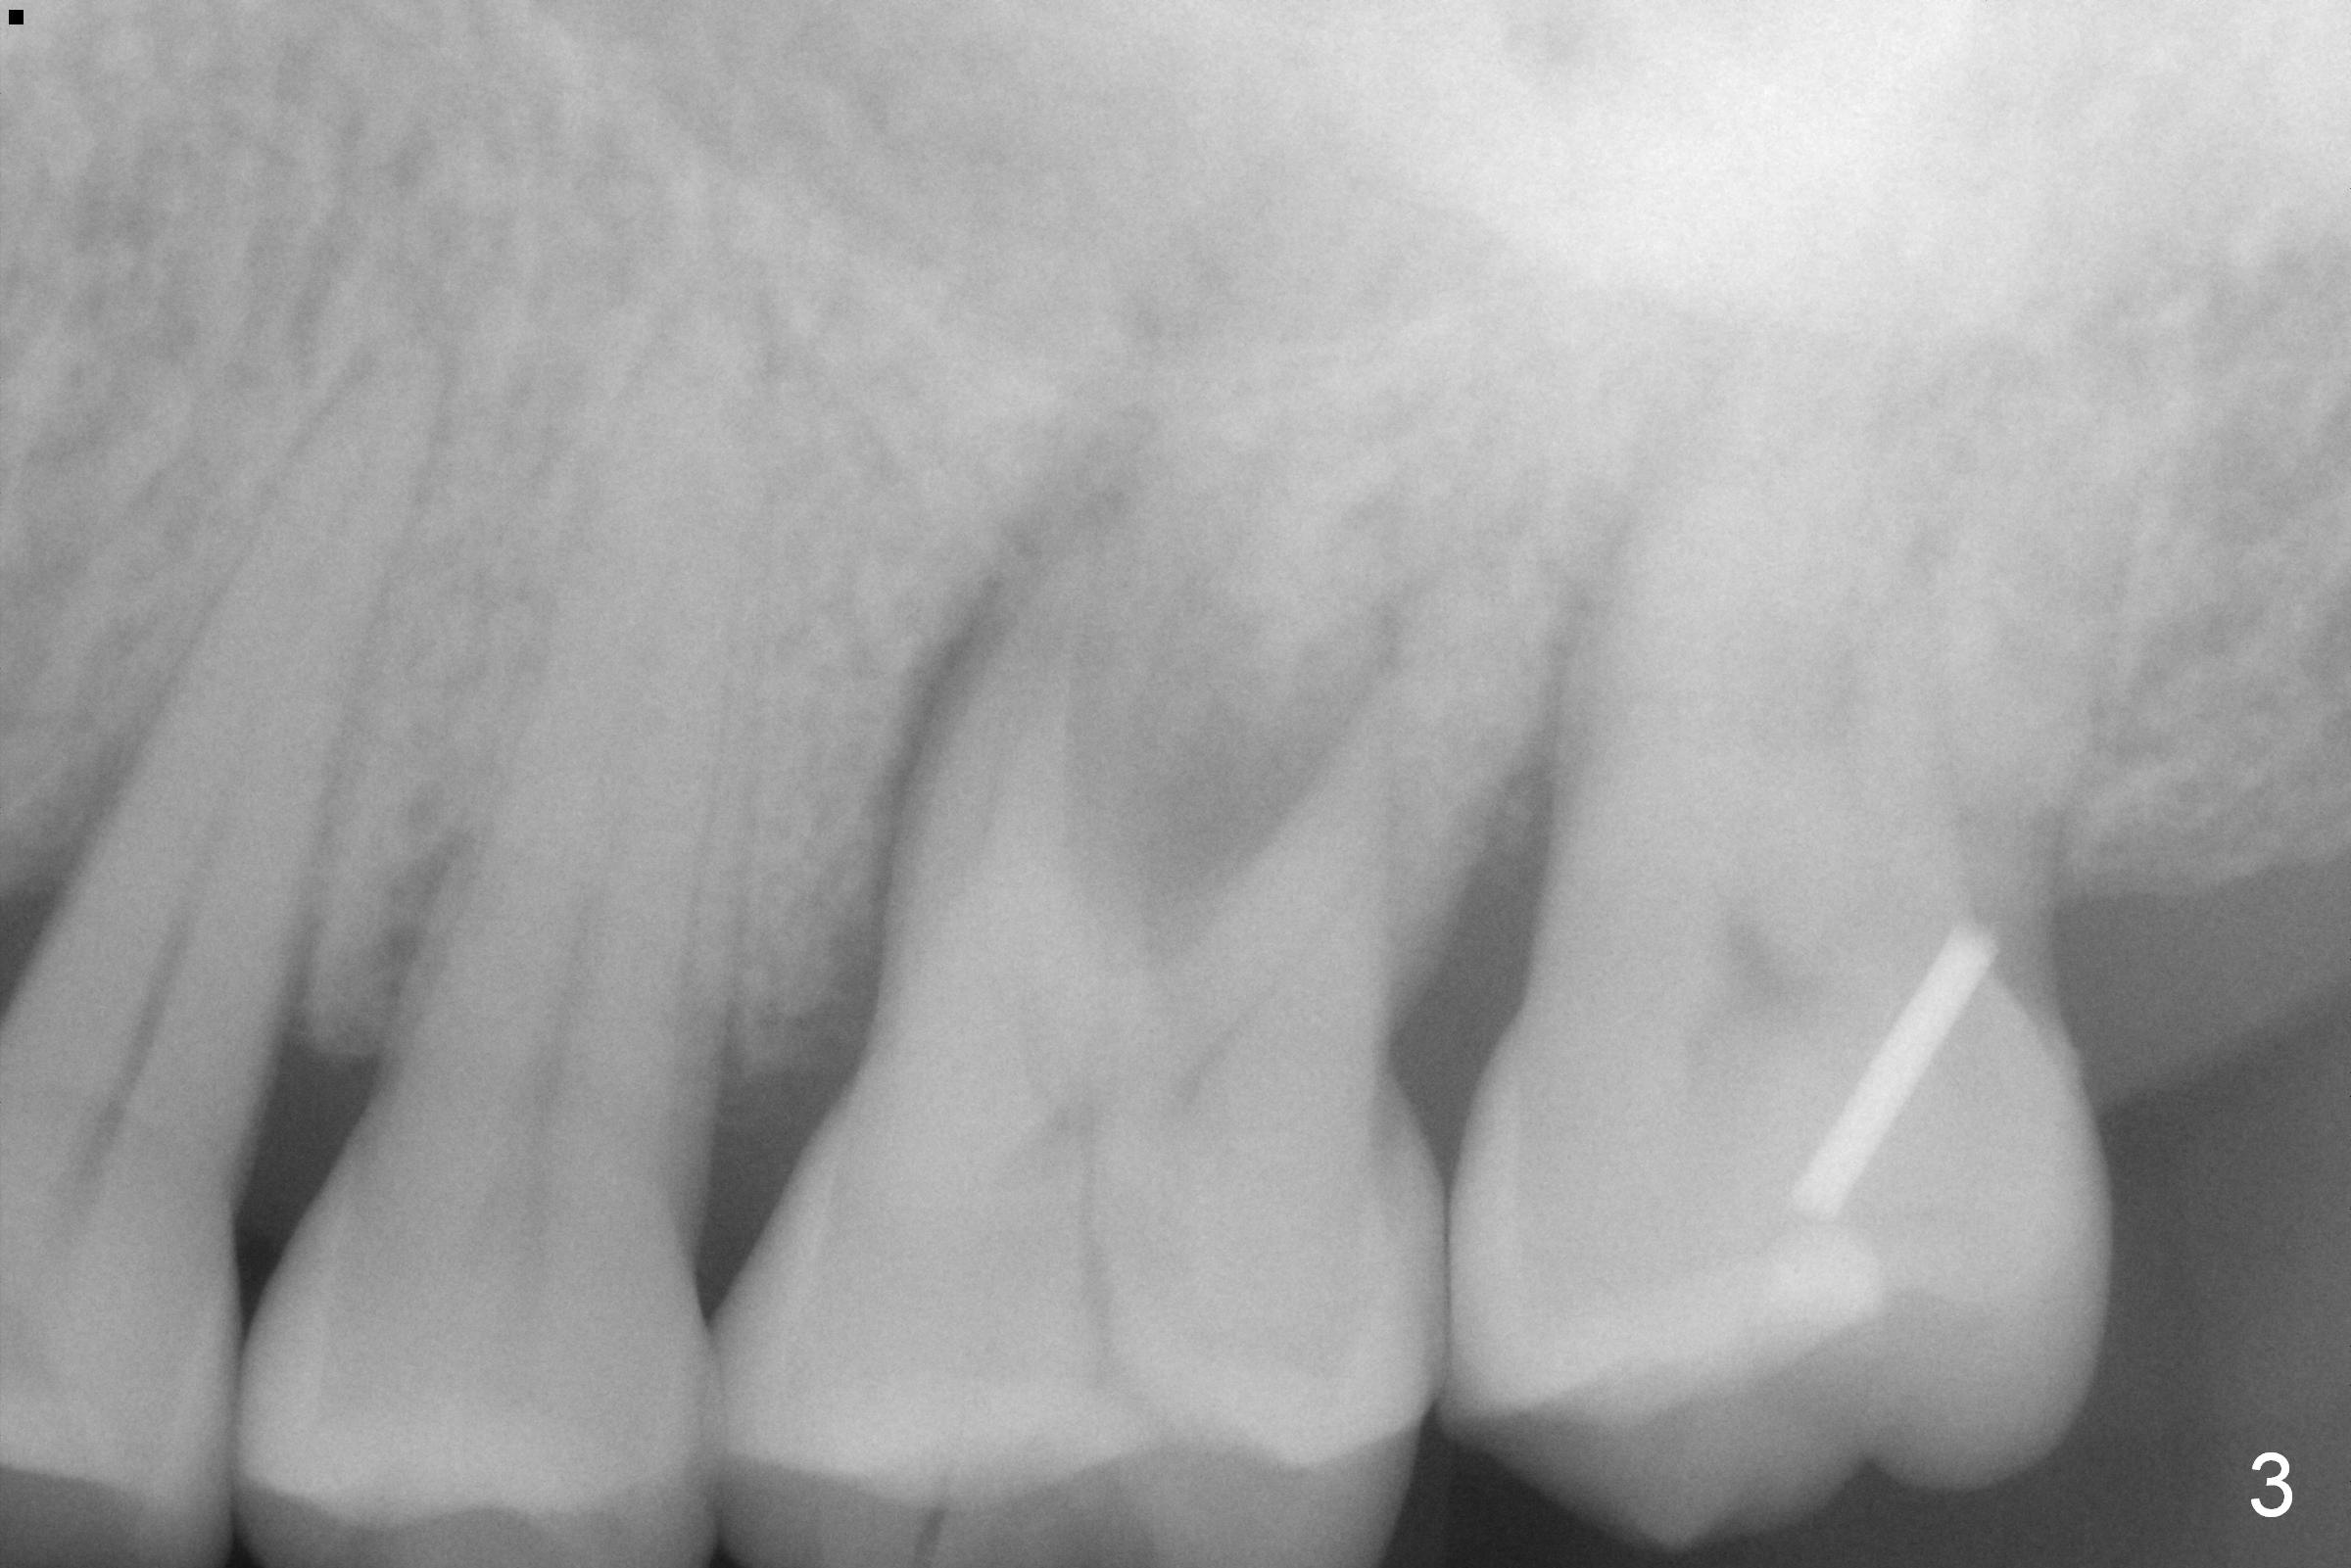

A 54-year-old lady has history of chronic periodontitis, characterized by bone loss (Fig.1 <, 2) . Her oral hygiene is fair. Bone loss and obliterated canals at #14 (Fig.1) are apparently related to bruxism. The latter seems to cause crack tooth at #15 with infection lately (Fig.3). Since the bone height is plenty (Fig.4), the longest implant will be used (5-7x20 mm (tissue-level) or 5.5x13 mm or longer (bone-level, Fig.5)). Use 2 mm drill to measure the socket (Metronidazole) depth and osteotomy will be at least 6 mm in the new bone. In fact, the tooth #14 is found to be affected when the patient returns from a periodontist's office (Fig.3).